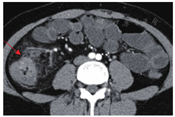

患者女性,24岁,因"全血细胞减少13年、腹痛、腹泻1年余"于2018年6月就诊。患者2005年(11岁)因鼻出血发现全血细胞减少,血常规示WBC 3.7×109/L、HGB 70 g/L、PLT 30×109/L,诊断"再生障碍性贫血",予泼尼松、环孢素A、雄激素、静脉丙种球蛋白治疗,效果均不佳,监测血常规示WBC (2~5)×109/L,HGB 60~90 g/L,PLT (10~20)×109/L,逐渐出现输血依赖,期间环孢素A联合雄激素治疗约10年,2016年停药。2016年外周血染色体断裂试验示染色体断裂异常(丝裂霉素C 50 ng/ml刺激下断裂率26%),彗星试验示骨髓细胞DNA存在损伤(彗星细胞率18%)。2017年1月无明显诱因反复发生右下腹痛、腹泻,间断排少量暗红色血便,伴间断发热,血常规示WBC 3.73×109/L、HGB 38 g/L、PLT 5×109/L、网织红细胞1.72%;粪便潜血阳性;铁蛋白3 185 μg/L(参考值14~307 μg/L),C反应蛋白67 mg/L(参考值<8 mg/L),肝肾功正常;抗核抗体、抗可溶性核抗原(ENA)阴性,CD55、CD59表达100%。骨髓涂片:增生减低,粒红比1.19∶1,淋巴细胞比例增高,全片共见巨核细胞2个,为成熟无血小板形成巨核细胞,骨髓小粒以非造血细胞为主。骨髓活检:骨髓增生极度低下,脂肪细胞增生,巨核细胞少见。染色体核型:46,XX[20]。血液系统疾病基因突变筛查:IL7R S105N突变,JAK2 E890K突变。腹部增强CT:升结肠、盲肠、回肠末端及阑尾病变,肠系膜淋巴结肿大。因血细胞减少明显加重但肠道病变性质不明无法行移植造血干细胞,2017年1月再次开始予以环孢素A 150 mg/d、达那唑0.6 g/d治疗;予抗生素治疗后患者腹痛、发热好转,但仍反复出现。2017年11月及2018年1月两次行结肠镜检查:升结肠可见巨大环周增殖性病变,表面长10 cm、累及回盲瓣、质硬巨大溃疡(图1);活检病理:肠黏膜显重度急性及慢性炎症,淋巴组织高度增生,伴溃疡及肉芽组织形成,考虑为不典型淋巴组织增生性疾病;免疫组化:CD20(+),CD3(+),CD10(-),PAX-5(+),CD 79a(+),Bcl2(+),Ki-67(局灶40%+);IgH、IgK基因克隆性重排阴性。2018年1月PET-CT(图2):回盲部及邻近升结肠壁厚,局部代谢增高(SUV值11.5)。为进一步诊治于2018年4月就诊于我院。既往史:反复输注红细胞、血小板。个人史:患者出生时左小腿、左足皮肤松弛、淤青,随生长发育出现左小腿较右侧粗、足各脚趾较右侧粗短,智力发育正常。家族史:父母体健,胞姐1周岁时诊断再生障碍性贫血,2岁时夭折,胞弟体健。

查体:身高167 cm,左足各脚趾较右侧粗短,左小腿较右侧粗;贫血貌,皮肤未见瘀点、瘀斑,全身浅表淋巴结未触及肿大,腹部无压痛、反跳痛,肝脾肋缘下未触及。外周血高通量基因二代测序发现MPL基因复合杂合突变(表1、图3)。2018年4月加用沙利度胺100 mg/d口服,并继续间断输血支持、重组人粒细胞集落刺激因子(G-CSF)、重组人血小板生成素(TPO)、重组人红细胞生成素(EPO)治疗。患者未再出现便血,偶有腹痛,因白细胞低间断有发热,粪便潜血持续阳性。2018年8月血常规:WBC 2.48×109/L,中性粒细胞绝对值0.68×109/L,HGB 69 g/L,PLT 14×109/L。PPD试验及淋巴细胞干扰素试验阴性。腹盆增强CT+小肠重建:升结肠肠壁弥漫增厚伴异常强化,符合淋巴瘤表现,邻近肠系膜区多发淋巴结(图4)。结肠镜:回盲部局部可见溃疡型病变,周围黏膜纠集、结节感,较前明显减轻,回盲部结构破坏、变形(图5);活检病理:结肠黏膜急性及慢性炎症伴肉芽组织形成;免疫组化:AE1/AE3(上皮+),CD3(散在+),CD20(散在+),CD31(血管+),CD68(散在+),Ki-67(index 5%)。原位杂交:CMV ISH(-),EBER ISH(-)。肠道病变随访2年余,3次活检病理不符合淋巴瘤诊断,沙利度胺治疗后好转,临床诊断为肠白塞病。2019年7月在外院行父供女单倍型造血干细胞移植,移植后1个月粒细胞植活,但并发出血性膀胱炎,输血、输血小板依赖,2019年11月死亡,未行尸检。